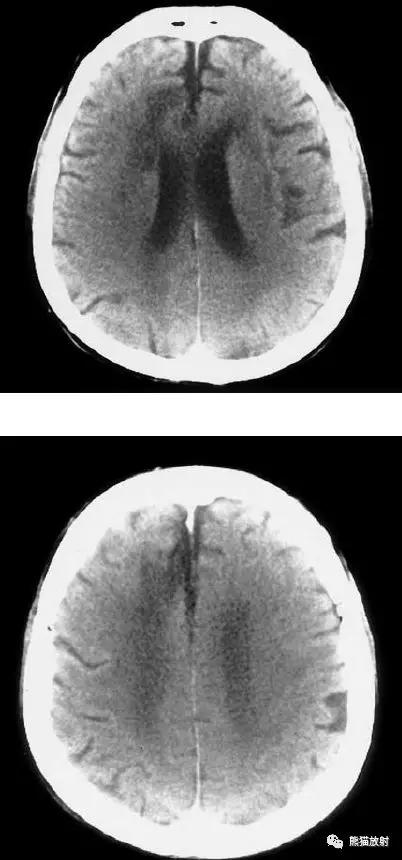

右侧大脑中动脉区域梗死的典型演变:

a)急性期

b)早期亚急性期(2天,从临床起病开始)

c)亚急性晚期(2周后)

d)慢性期(一年后)